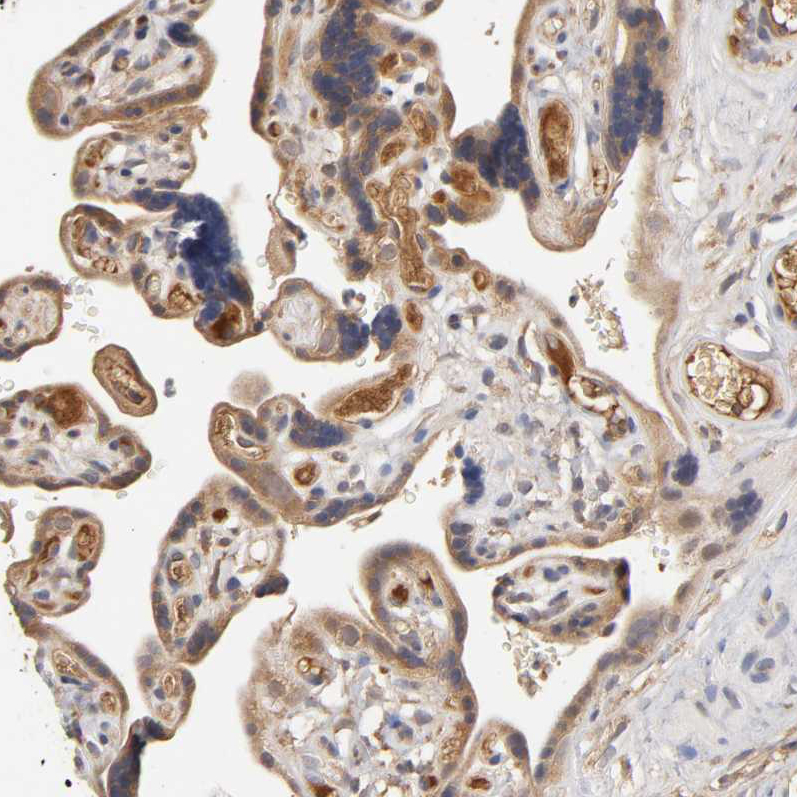

Immunohistochemical staining of human pancreas shows strong cytoplasmic positivity in exocrine glandular cells.